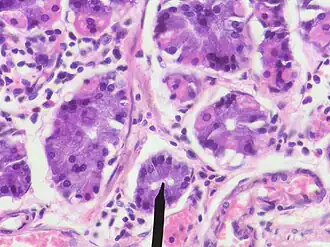

Гла́вные кле́тки (синонимы: зимогенные клетки, главные гландулоциты) — клетки слизистой оболочки желудка, секретирующие профермент пепсина пепсиноген, желудочную липазу, устойчивую в кислой среде, а также профермент реннина (химозина).

Главные клетки располагаются в фундальных (главных) железах желудка. Фундальные (синоним главные) железы составляют основную часть желёз области дна, тела и интермедиарной зоны желудка.